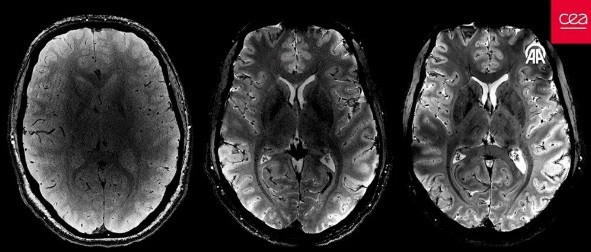

CEA'dan yapılan yazılı açıklamada "Iseult" adlı MRI cihazıyla çekilen beyin görüntüsünün 20 yıldan uzun süren bir çalışma sonucu elde edildiği belirtildi.

Yapılan çalışmalar kapsamında MRI cihazının son birkaç ay içerisinde yaklaşık 20 sağlıklı gönüllü üzerinde test edildiği kaydedilen açıklamada, neredeyse 4 dakikada en net beyin görüntüsünün elde edildiği aktarıldı.

Açıklamada, 11,7 Tesla manyetik güce sahip Iseult MRI makinesiyle kısa sürede çekilen görüntülerin, hastanelerde yaygın kullanılan cihazlarla elde edilmesinin saatler sürebileceği kaydedildi.